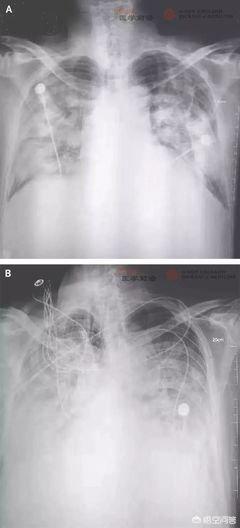

Il n'y a pas de fièvre, de fatigue, de toux, de dyspnée ; caractéristiques d'imagerie : au début, la maladie présente de multiples petites zones d'ombre et des changements interstitiels, les bandes externes des poumons étant évidentes. Elle évolue ensuite vers de multiples ombres en verre pilé et des ombres d'infiltration dans les deux poumons, et dans les cas graves, des modifications pulmonaires solides peuvent apparaître, l'épanchement pleural étant rare. Prise de sang et autres tests de laboratoire : le nombre total de leucocytes du sang périphérique est normal ou réduit au stade précoce de la maladie, le nombre de lymphocytes est réduit, et les enzymes hépatiques, les enzymes musculaires et la myoglobine sont augmentés chez certains patients. La protéine C-réactive (CRP) et la sédimentation sanguine sont élevées chez la plupart des patients, et le calcitoninogène est normal. Dans les cas graves, les D-dimères sont élevés et les lymphocytes du sang périphérique diminuent progressivement. Les nouveaux acides nucléiques du coronavirus peuvent être détectés dans des échantillons tels que les écouvillons pharyngés, les expectorations, les sécrétions des voies respiratoires inférieures et le sang.

Si les patients infectés par une nouvelle pneumonie à coronavirus passent une tomodensitométrie pulmonaire, le stade précoce suggérera de multiples petites zones d'ombre et des changements interstitiels dans les bandes externes des poumons, puis évoluera vers des poumons bilatéraux avec de multiples zones d'ombre en verre dépoli, des zones d'ombre d'infiltration, les cas graves peuvent apparaître des changements solides dans les poumons, l'épanchement pleural est rare ; si l'analyse sanguine de routine, le nombre total de leucocytes du sang périphérique au stade précoce est normal ou réduit, le nombre de lymphocytes est réduit, et les tests biochimiques de certains patients montreront des enzymes hépatiques, de la myosinase et de la myoglobine en plus de leur nombre. Certains patients peuvent présenter une augmentation des enzymes hépatiques, des enzymes musculaires et de la myoglobine. Chez la plupart des patients, la protéine C-réactive et la vitesse de sédimentation sont élevées, le calcitoninogène est normal et les lymphocytes diminuent progressivement.

Manifestations cliniques : 1. fièvre ; 2. changements dans l'imagerie de la pneumonie dans les poumons ; 3. diminution ou normalisation du nombre total de globules blancs ou diminution du nombre de lymphocytes au début de l'évolution de la maladie.